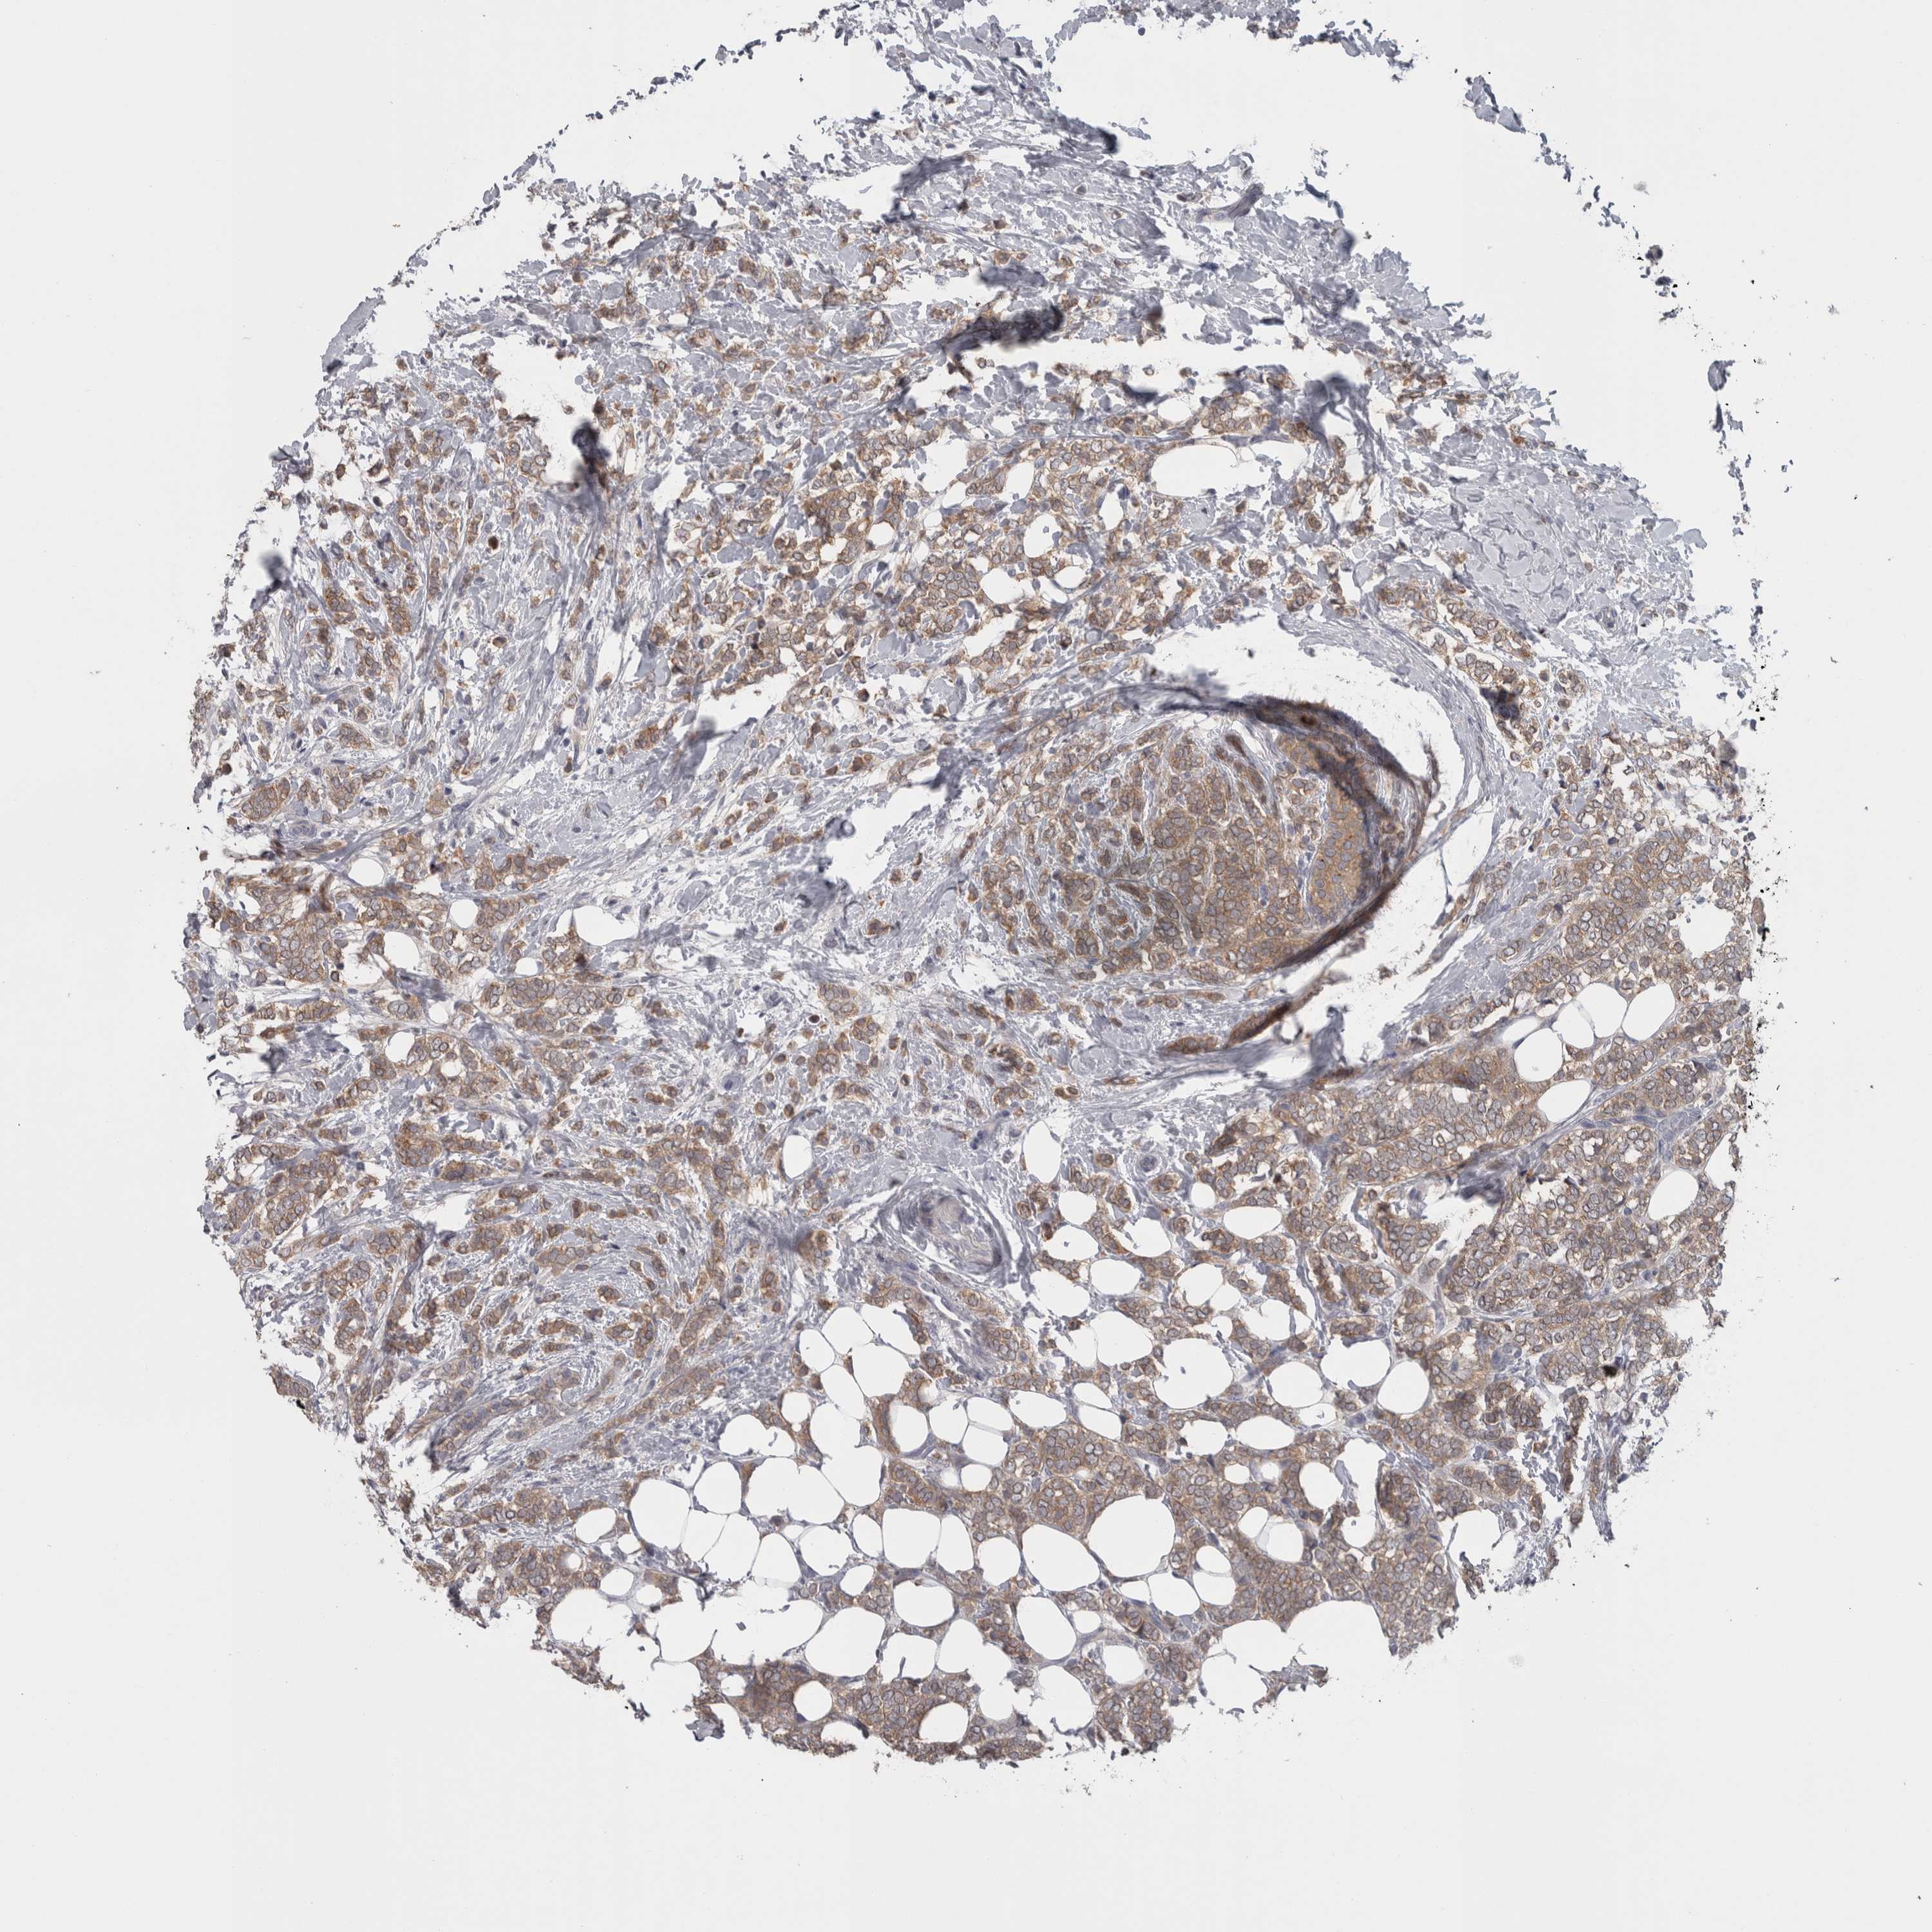

CANCER BREAST CANCER Show tissue menu

BRCA TCGA BRCA VALIDATION PROTEIN EXPRESSION